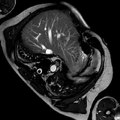

The KORA 100 MRI conditional pacing system offers the only MRI mode that automatically detects an MRI magnetic field, provides safe MRI scanning, then follows with an automatic return to normal operation when the patient leaves the MRI environment.